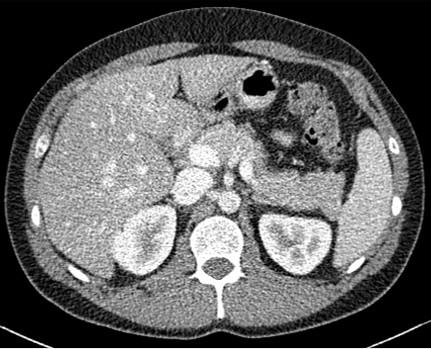

Figure 2: Comparison of generated Pseudo-LDCT images and their noise. (a) LDCT, (b) Random noise histogram, (c) Gaussian noise, (d) Ours. The right-bottom patch indicates the noise lying on each image. The noise quality of (b) and (c) shows that random noise cannot represent (a). In contrast, (d) shows almost similar to (a)

For evaluation, the 2016 AAPM Low-Dose CT Grand Challenge dataset[16] was used and split into 3 train and 7 test, respectively. It consists of abdominal LDCT and NDCT images obtained from 10 patients with image size 512×512512512512\times 512. The voxel space of CT images is 0.5mm×0.5mm0.5𝑚𝑚0.5𝑚𝑚0.5mm\times 0.5mm with 3mm3𝑚𝑚3mm slice thickness. To demonstrate that our method works with any existing learning method, we applied our method to N2C (Noise2Clean), N2N (Noise2Noise)[13], and N2V (Noise2Void)[11]. N2C is a supervised learning method that uses all available labeled paired data. N2N and N2V are self-supervised learning methods which use noisy pair images and masking schemes. Also, to demonstrate the effectiveness of our noise model, we compared LDCT denoising performance against existing noise generation techniques i.e. Random Noise histogram (Hist), Gaussian noise (Gaussian), and Single noise model++Noise histogram (Model+Hist). Hist samples noise from the difference map based on the histogram between LDCT and NDCT images, whereas gaussian samples the noise from a Gaussian distribution with zero mean and 0.02 standard deviation. Model+Hist is the combination of a single pre-trained LDCT noise model (using all subjects in the training dataset) and Hist. For evaluation, Peak Signal-to-Noise Ratio (PSNR) and Structural Similarity (SSIM) are reported.

For parameter updates, it is crucial to generate high-quality Pseudo-LDCT images i.e. images similar to an actual LDCT image. If high-quality Pseudo-LDCT images are provided to the model for training, CT denoising performance can be improved. In contrast, using low-quality Pseudo-CT images may adversely affects the model learning, and consequently lead to decreased denoising performance. Table. 1 also shows the average PSNR and SSIM in different Pseudo-CT image generation settings. Here, both Hist and Gaussian reported lower performance compared to N2C. Based on our observations, this serves to show that random noise employed in natural images is not useful for CT denoising. In contrast, when our noise model was combined with Hist i.e. Model+Hist, performance gains over N2C were noted. This implies that our noise model can generate reasonable noise similar to the actual CT noise, and also improves performance. Furthermore, our ensemble noise models without parameter update show improved results over Model+Hist without the need for additional random noise.

In Figures 2 and 3, we show comparison results of Pseudo-LDCT images and their generated noise using various methods, as well as the predictions of our method for each. In Fig. 2, Pseudo-LDCT images and their noise with Hist and Gaussian highlight a huge discrepancy between the actual LDCT image and its noise. In the case of random noise that is shown to be independently distributed across the entire image, it is often useful for natural image denoising. Moreover, this types of noise does not accurately reflect the nature of CT images. Through the proposed method, we show it is possible to generate Pseudo-CT images that preserve overall CT image characteristics with high quality (Fig. 3).